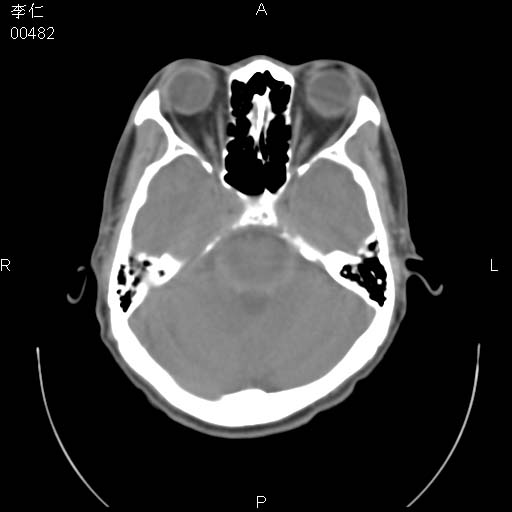

患者男,45岁。于二月前发现左眼稍肿,去看眼科,查肾功(—),来查ct,我看到的是左侧上眼睑内低密度影,ct值是-600到-700hu。

副鼻窦发育畸形所致。

是气体 前组筛窦发育过度所致,如果有外伤就不排除骨折

是一个副鼻窦的正常变异,脂肪瘤的密度不可能这么低,-600到-700.

副鼻窦的正常变异